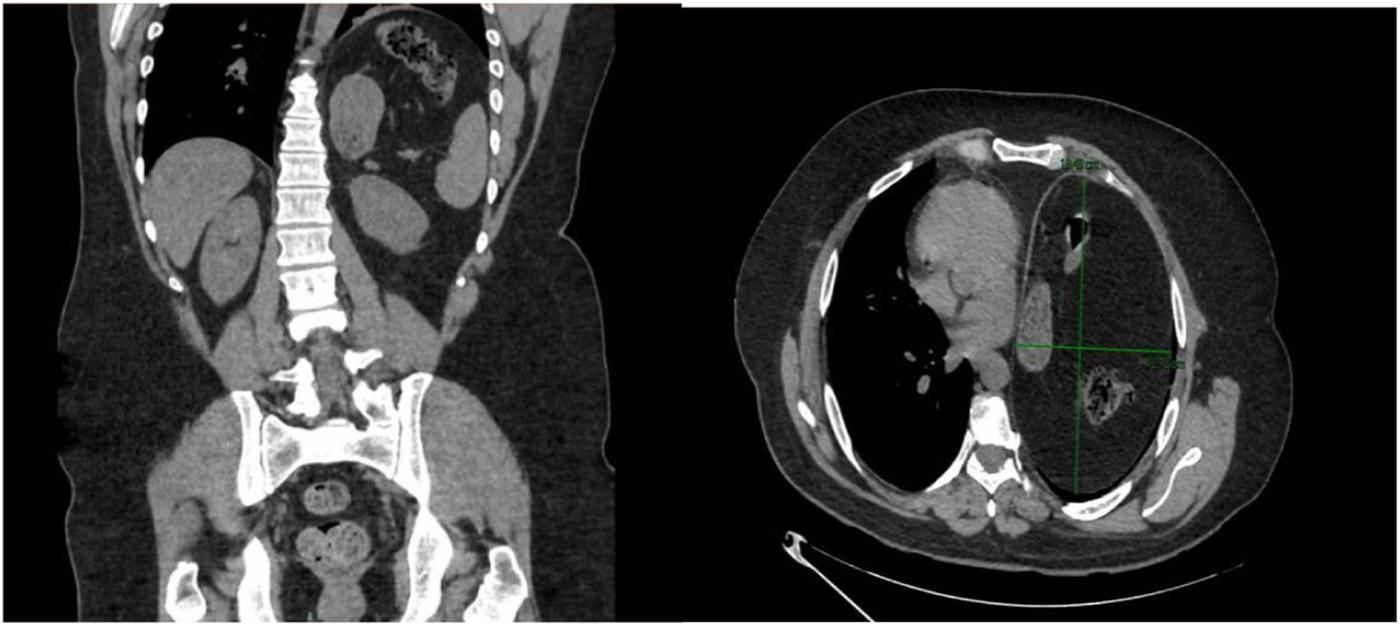

A neurophysiological study and thoracic computed tomography scan (Figure 1) revealed a serious elevation of the left hemidiaphragm and herniation of abdominal contents into the thorax, including stomach, spleen, and colon splenic flexure, occupying approximately 50% of the left hemithorax and causing right mediastinal shift, with 20% of abdominal viscera displaced into the thorax according to Sabagg’s formula [13]. Preoperative preparation focused on prehabilitation with respiratory physiotherapy.

FIGURE 1

Computed tomography scan (coronal and transverse section). Significant elevation of the left hemidiaphragm and infradiaphragmatic abdominal contents, including the stomach, spleen, and splenic flexure of the colon and deviation of the mediastinum to the right.